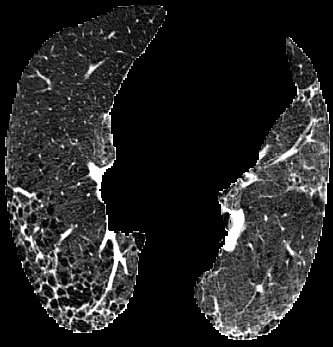

In the field of medical imaging, particularly in tasks related to early disease detection and prognosis, understanding the reasoning behind AI model predictions is imperative for assessing their reliability. Conventional explanation methods encounter challenges in identifying decisive features in medical image classifications, especially when discriminative features are subtle or not immediately evident. To address this limitation, we propose an agent model capable of generating counterfactual images that prompt different decisions when plugged into a black box model. By employing this agent model, we can uncover influential image patterns that impact the black model's final predictions. Through our methodology, we efficiently identify features that influence decisions of the deep black box. We validated our approach in the rigorous domain of medical prognosis tasks, showcasing its efficacy and potential to enhance the reliability of deep learning models in medical image classification compared to existing interpretation methods. The code will be publicly available at https://github.com/ayanglab/DiffExplainer.